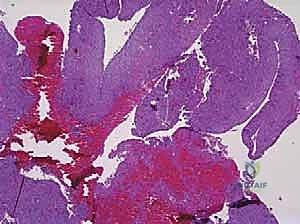

* التكوين النسيجي: لا يحتوي على سائل صافٍ، بل يحتوي على مساحات كيسية متعددة مملوءة بالدم. من الناحية المجهرية، هذه المساحات ليست أوعية دموية حقيقية (تفتقر للبطانة الوعائية)، بل تفصلها حواجز ليفية تحتوي على خلايا عملاقة (Giant Cells) وعظم غير ناضج. هذا التمييز النسيجي حاسم لفهم سبب نزيفها الشديد أثناء الجراحة وطبيعتها العدوانية.

صورة مجهرية توضح الفحص النسيجي لكيس العظم المتمدد (ABC)، حيث تظهر الحواجز الليفية والخلايا العملاقة التي تحيط بالمساحات المليئة بالدم، وهو ما يفسر السلوك العدواني الموضعي لهذا النوع من الأكياس.